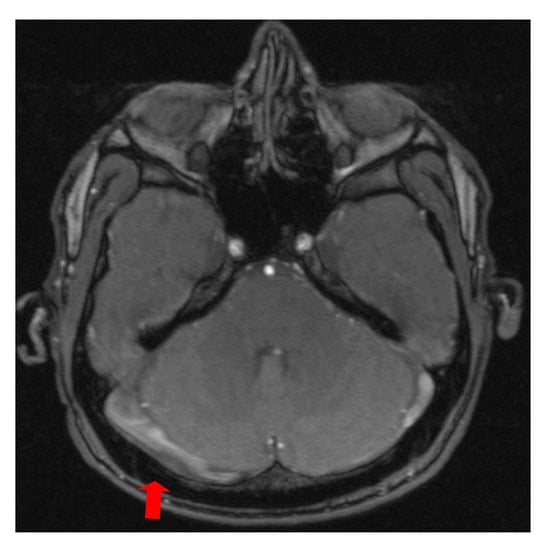

The second case was a female, 31 years old, with an etiology of thrombophlebitis accentuated by the presence of the MTHFR C677T gene polymorphism- homozygous phenotype. The patient was hospitalized with superficial coma, generalized seizures and left hemiparesis. In the course of evolution, subsequent to the cerebral post thrombotic syndrome and edematous encephalopathy, the patient presented symptomatology characterized by generalized seizures under anticonvulsivant treatment and also psychical disturbances (irritability, aggressiveness). The patient was clinically and neuroimagistic assessed after six month and six years from the onset of the disease. The image features can be seen in Figure 3, Figure 4 and Figure 5.

Figure 4. MR- venography 3D- TOF (time of flight) reveals subarachnoid hemorrhage which accompanies superior sagittal sinus and right lateral sinus thrombophlebitis.